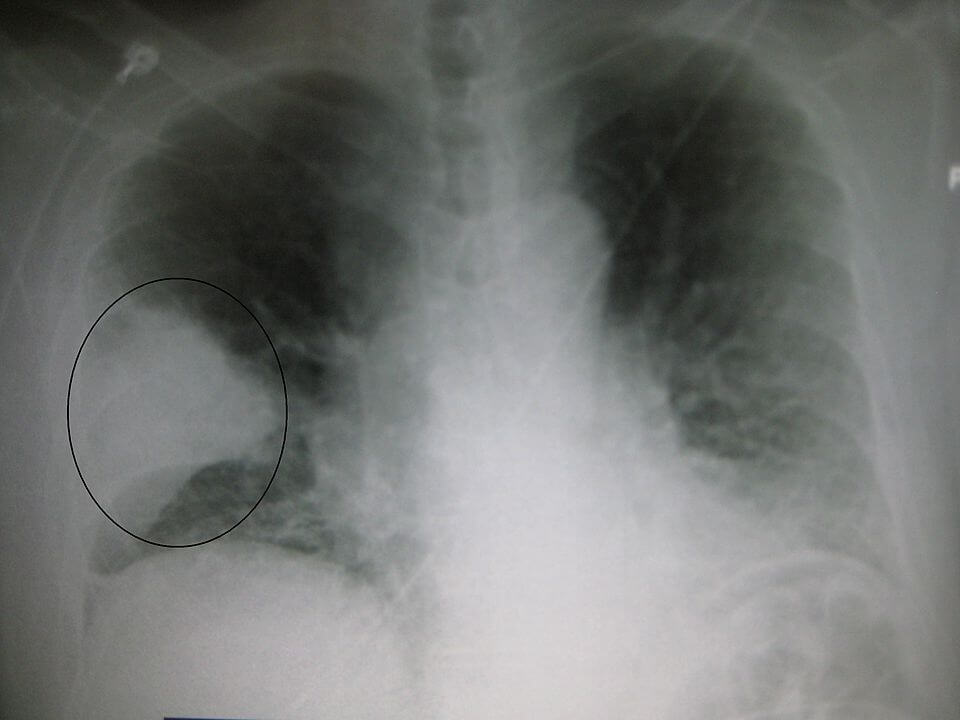

Pneumonia หรือ โรคปอดอักเสบเรื้อรัง ปอดบวม เป็นโรคที่พบได้ประมาณร้อยละ 8-10 ของผู้ป่วยที่มีการติดเชื้อเฉียบพลันระบบหายใจ นับเป็นสาเหตุการตายอันดับหนึ่งของโรคติดเชื้อในเด็กอายุต่ำกว่า 5 ปี เกิดจากสาเหตุหลัก 2 กลุ่ม คือ ปอดอักเสบที่เกิดจากการติดเชื้อและปอดอักเสบที่ไม่ได้เกิดจากการติดเชื้อ ถ้าเราสามารถพัฒนาระบบ AI ช่วยวินิจฉัยโรคเบื้องต้น จำแนกชนิดของโรค Pneumonia จะมีประโยชน์ในการวินิจฉัย และดูแลรักษาตั้งแต่แรก

DICOM คืออะไร โปรแกรมเปิดไฟล์ ภาพถ่ายทางการแพทย์ Mdical Imaging MRI, X-Ray, CT-Scan, Ultrasound วินิจฉัยโรคปอดรั่ว Pneumothorax จากฟิล์ม X-Ray DICOM ด้วย Deep Learning – Image Classification ep.9

ในการพัฒนาระบบ AI สำหรับวินิจฉัยโรค ชนิดของข้อมูล Dataset ที่เราจะพบบ่อย ๆ หนึ่งในนั้นคือไฟล์ DICOM ซึ่งเป็นไฟล์ภาพถ่ายทางการแพทย์ Mdical Imaging สำหรับฟิล์ม X-Ray, MRI, CT-Scan, Ultrasound ใน ep นี้เราจะมาทำความเข้าใจ ไฟล์ DICOM กันให้มากขึ้น